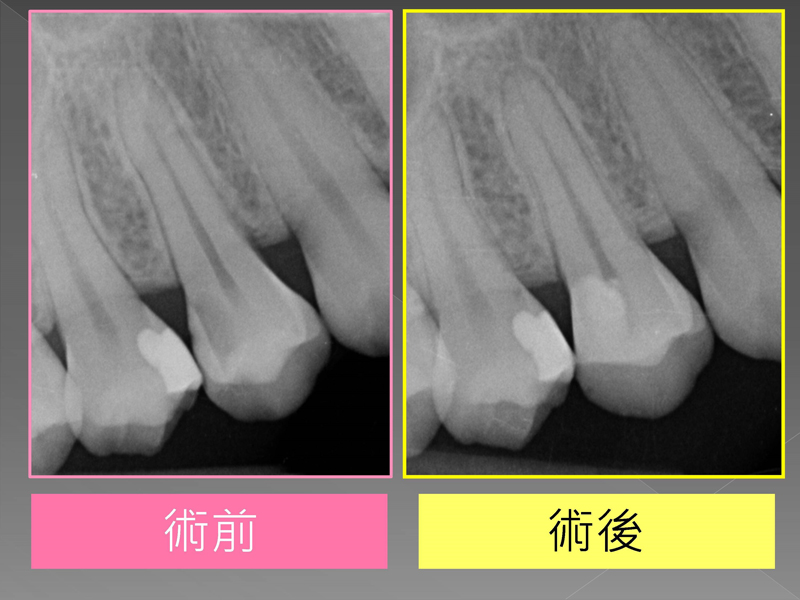

案例分享 首頁 案例分享 『植牙困難』案例分享 MORE 案例分享『矯正前之困難補骨』 MORE 案例分享『困難植牙』 MORE 案例分享『牙齒凌亂,不敢開懷大笑該怎麼辦?』 MORE 案例分享『斷裂器械移除』 MORE 案例分享『全口重建』 MORE 案例分享『活性牙髓治療(覆髓)- 蛀牙免根管治療的新選擇!』 MORE 案例分享『牙齒斷裂,利用水雷射補骨重建』 MORE 案例分享『上顎後牙區角質化上皮移植術(FGG)』 MORE 案例分享『第三代LITETOUCH水雷射舌繫帶切除』 MORE «1»